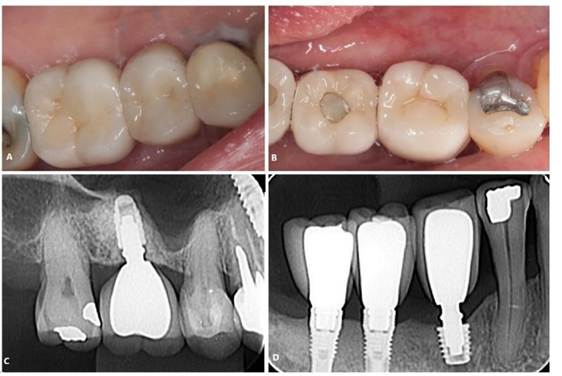

Inicialmente o bloqueio regional foi realizado utilizando anestésico local Alphacaíne 2% Lidocaína com Epinefrina 1:100.000 (DFL, Rio de Janeiro – RJ, Brasil). O procedimento cirúrgico seguiu-se pela incisão da região com lâmina 15, descolamento com instrumental Molt 9 (Quinelato, Rio Claro – SP, Brasil) e fresagem com broca Titamax 2.0 (Neodent, Curitiba – PR, Brasil), seguindo a sequência recomendada pelo fabricante. Após a instalação do implante curto, a sutura foi realizada com fio de nylon 4.0. O paciente foi instruído dos cuidados pós-operatórios, com prescrição medicamentosa de Amoxicilina 500mg de 8/8 horas por 7 dias, Nimesulida 100mg de 12/12 horas por 5 dias e Dipirona sódica 500mg de 4/4 horas por 3 dias. Ausência de complicações pós-operatórias foram evidenciadas (Figura 02. A,B)

Posteriormente, paciente foi reabilitado com prótese unitária sobre implantes (Figura 02. C,D) e o acompanhamento clínico e radiográfico (Figura 03. A, B) está sendo realizado até o presente momento, evidenciado resultado estável.

Figura 02. A, B) Etapa operatória da instalação do implante dental curto. C, D) Tratamento finalizado. Aspecto final com a reabilitação protética-implante.

Figura 03. A, B) Radiografias periapicais final.